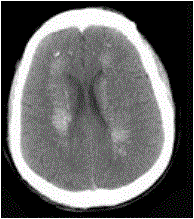

问题 男,52岁,无明显不适,CT检查如图所示,最可能的诊断为()

选项 A.脑血管畸形 B.结节性硬化 C.甲状旁腺低功能下 D.脑颜面血管瘤 E.转移瘤

答案 C